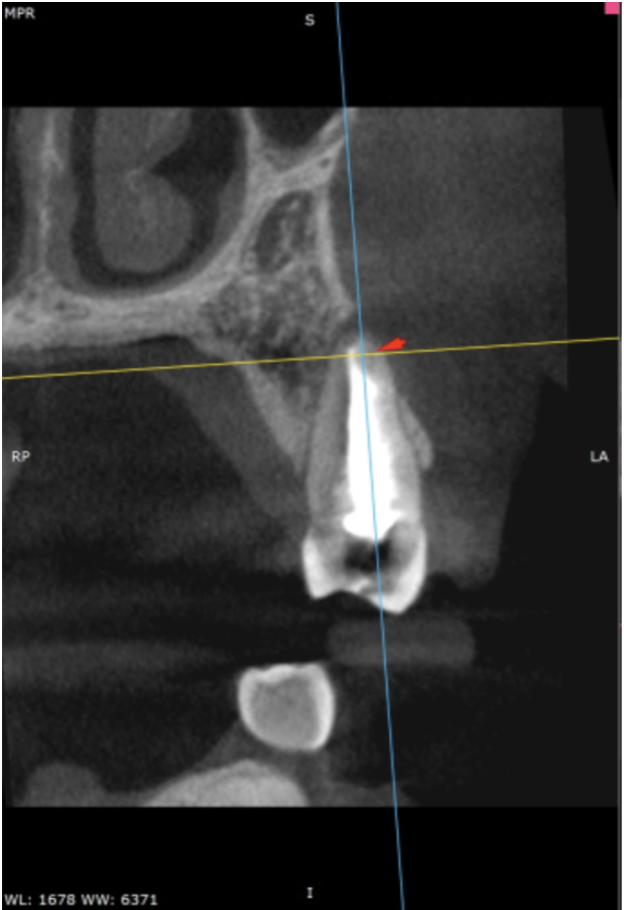

Pre-op IOPA & CBCT

This delightful lady was referred to me as she had recurrent pain and a firm apical swelling around her previously root-treated UL4. Upon viewing the IOPA, at first glance, this case appeared to have been adequately filled. However, CBCT review (shown above) highlighted a deep apical split of the main canal and an unfilled buccal branch, which seems like the most obvious reason for failure in this case.

Having this information preoperatively made the management of this case far more predictable and underlines why a small field of view high-resolution CBCT scan can be invaluable in the management of most re-treatment cases and arguably most primary cases too. Please follow the link for the most current guidance on the use of CBCT in endodontics (https://onlinelibrary.wiley.com/doi/10.1111/iej.13187). At the first visit, the existing root filling was removed using Reciproc blue R25 and prepped using R40 rotary files and the previously unfilled buccal branch was prepared with the reduced taper (4%) VDW Rotate 1504, 2005 and 2504 files, which is one of my favourite file systems. After lots of irrigation and PUI, the tooth was dressed using calcium hydroxide, and the tooth was well sealed for a month. The aim of this was to try and reduce the swelling and alleviate this lady’s symptoms, which it did really nicely. At the second visit, the tooth was further disinfected and re-obturated using WVC and TotalFill BC sealer Hiflow. It was then returned to the RD for cuspal coverage without delay. I plan to review this case in a year's time, so I will update this case study with new radiographs when I have them.